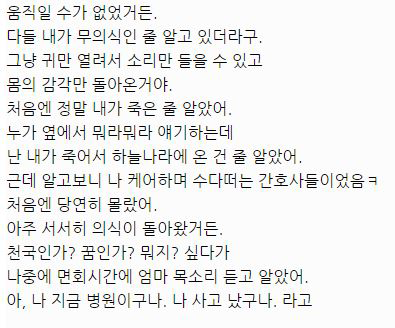

아래는 해당 글 작성자가 쓴 글.

대단한 얘기는 아니지만 중환자실에 3주동안 무의식으로 있었던 썰 풀어볼게